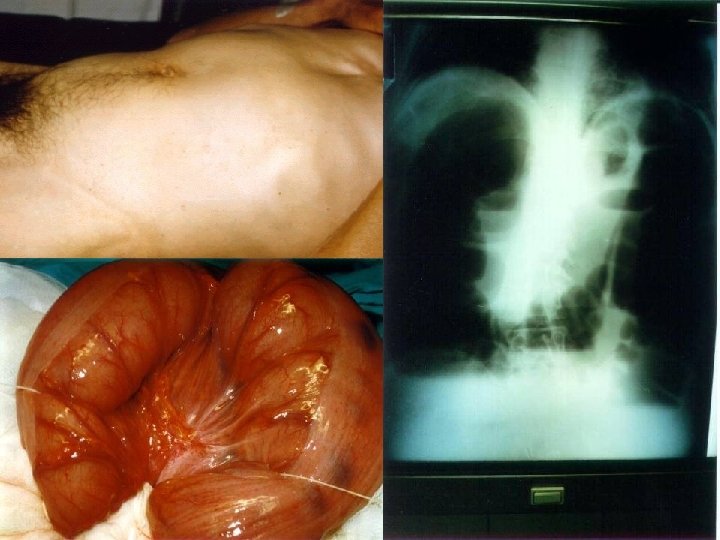

ESTUDIOS RADIOLÓGICOS Los Rayos X son esenciales para confirmar el diagnóstico clínico y definir con exactitud el lugar de la obstrucción. La Rx. de abdomen: Revela grandes cantidades de gas en el intestino y se puede casi siempre determinar si es el ID o IG el distendido o si ambos lo están.

Las radiografías de abdomen simple y en bipedestación muestra asas de intestino distendido con un patrón en escalera y niveles hidroáereos. El gas empieza a acumularse en el I. D. después de 3 hrs. del inicio de la obstrucción. Transcurridas 12 horas, casi siempre el I. D. estará distendido por gas y niveles líquidos ó ambos (obstrucción sea simple).

Px. Con Obs. Mecánica de ID: NO Presencia de gas en colon. Rx. Posición de pie o decúbito lateral: Niveles múltiples de gas y líquido, con distensión intestinal en forma de U invertida Rx. Abdomen con Obs. Colon más: § Válvula ileocecal competente: Distensión del colon § Válvula ileocecal incompetente: Distensión de ID y Colon.

Niveles Hidroaéreos

Radiografía de obstrucción del intestino delgado Íleo: Radiografía de la distensión intestinal